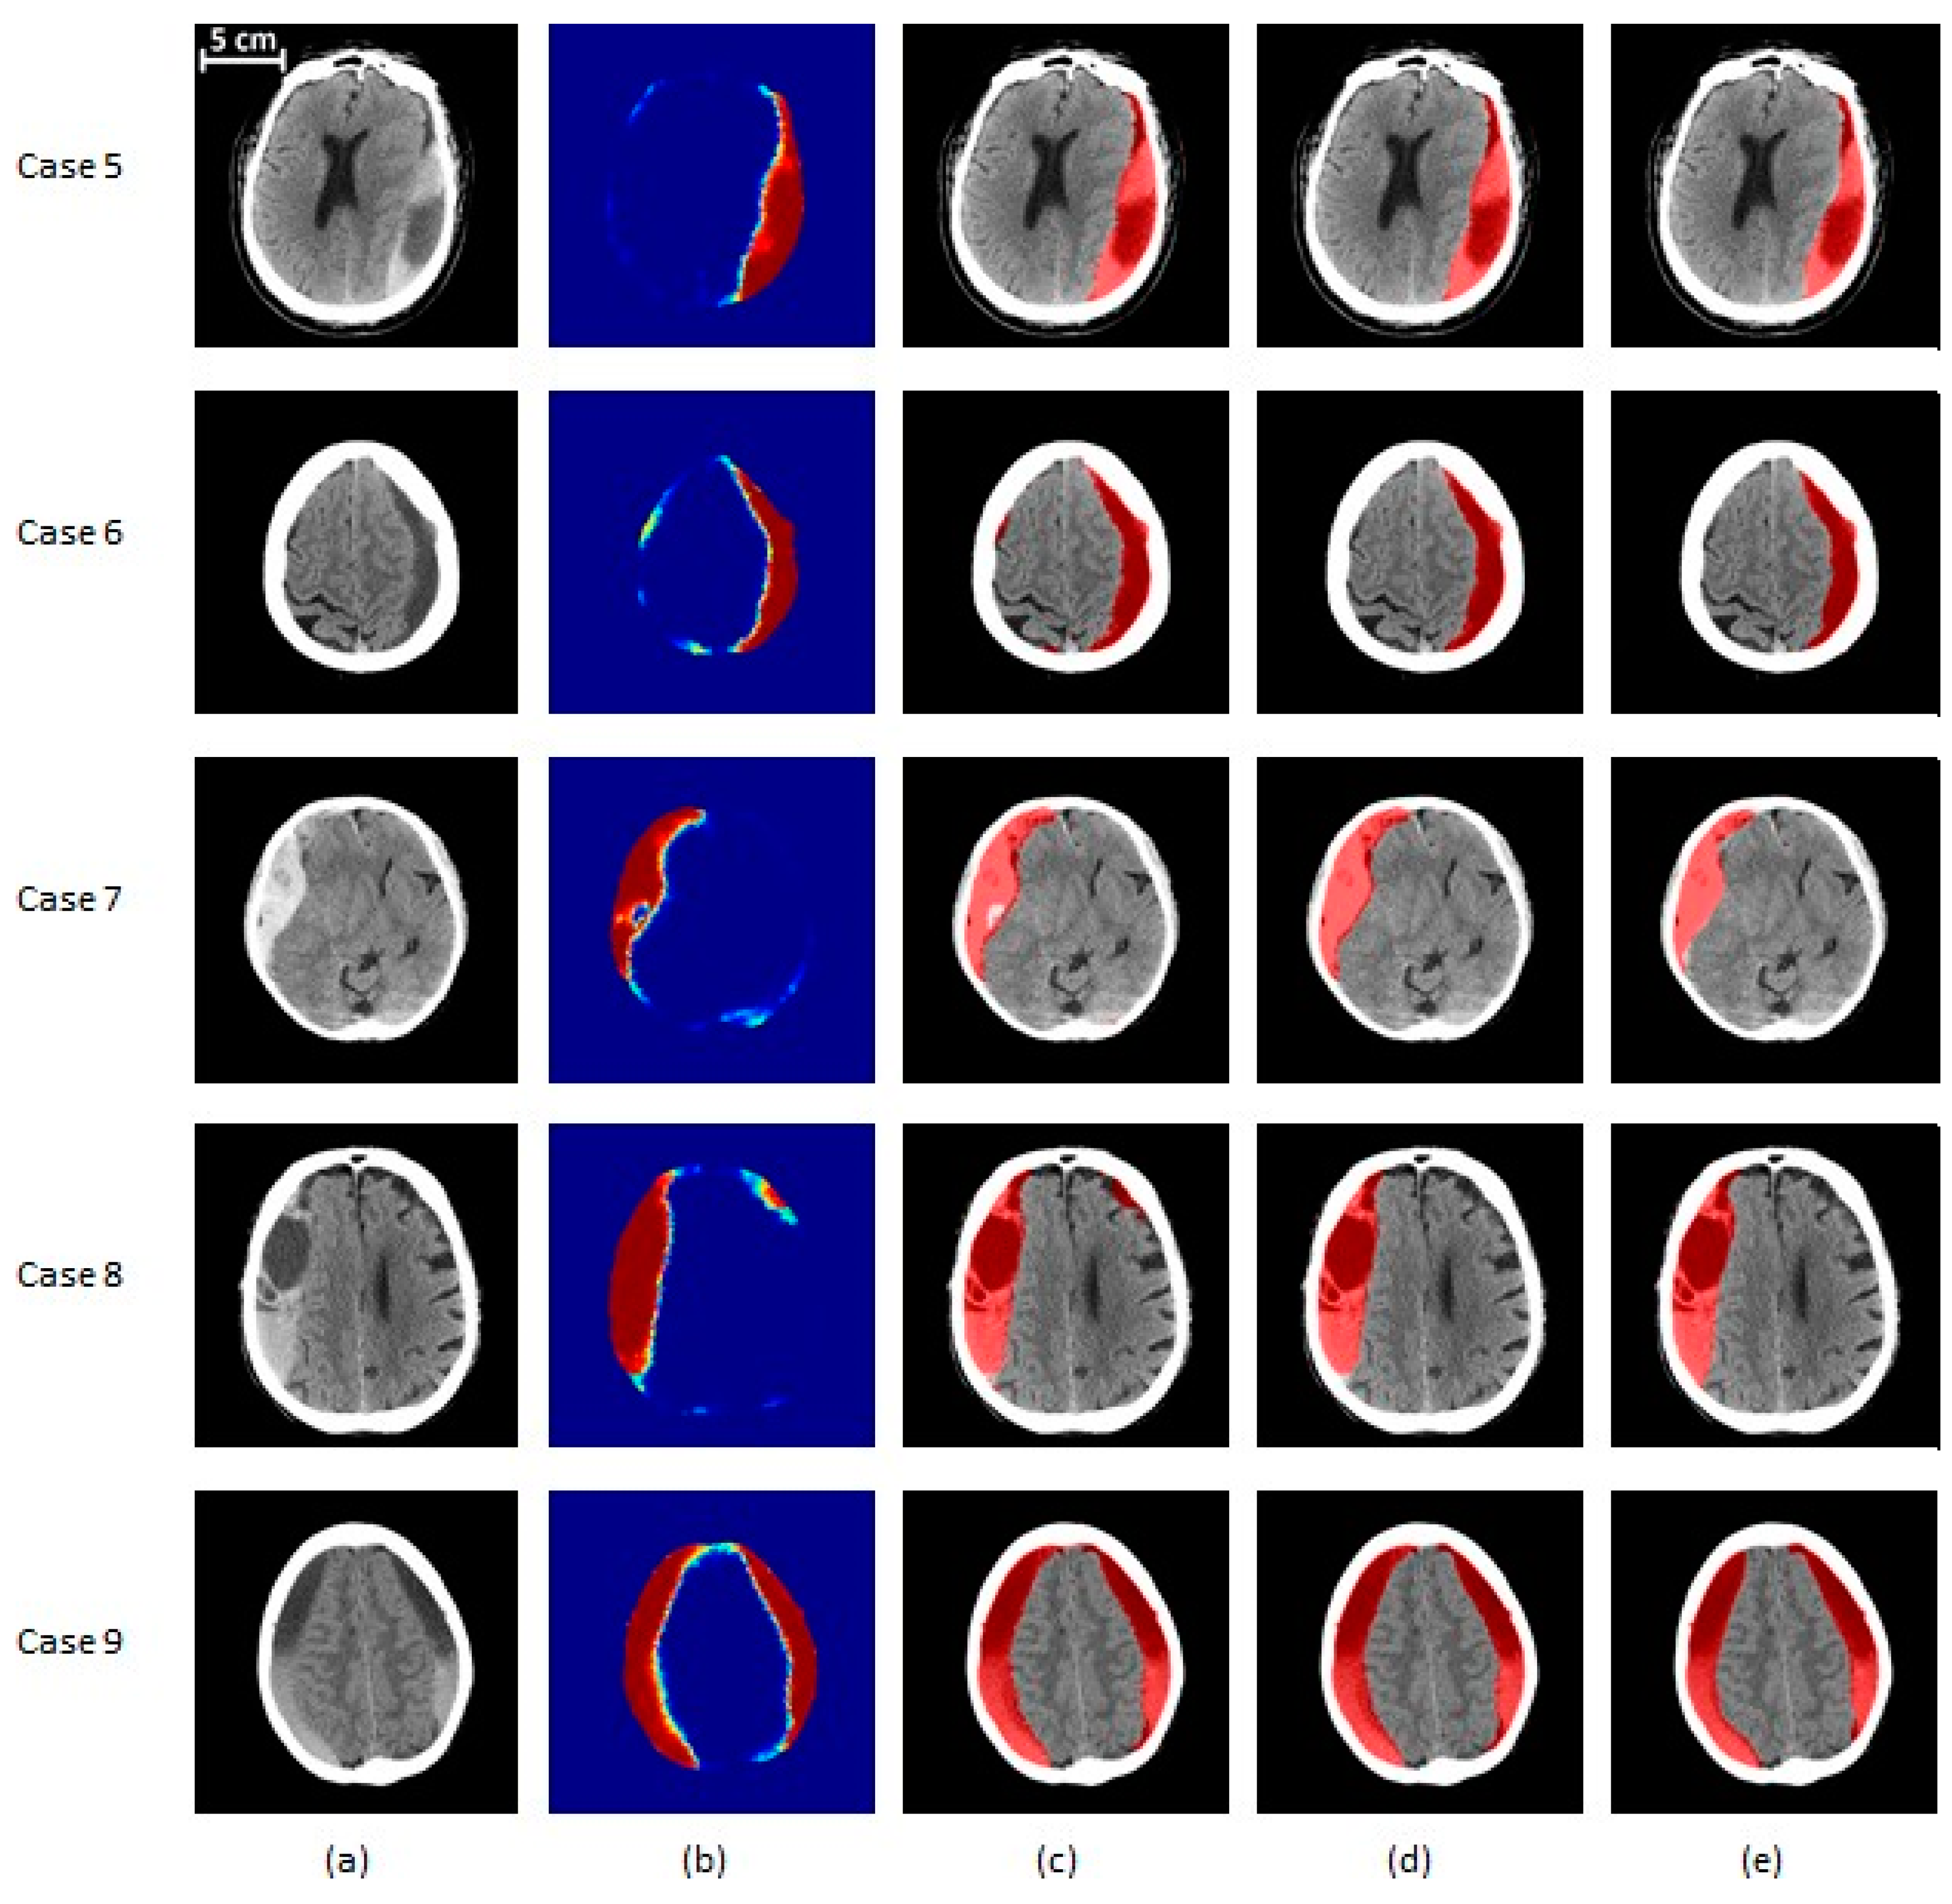

The results of the proposed segmentation algorithm at different stages are shown in

Figure 6 and

Figure 7. These images cover various combinations of size and type of subdural hematoma.

Figure 7.

SDH segmentation results on severe (>50 cc of blood) subjects. (a) The original CT image, (b) the probability map corresponding to the output of the classifier, (c) the segmented region before post-processing, (d) the segmentation result after post-processing, (e) the ground truth. Cases 5 and 6 are severe patients with total blood volume of less than 100 cc, while cases 7 and 8 have total blood volume of 100 to 200 cc. Finally, case 9’s SDH volume is over 200 cc. Cases 5, 8, and 9 contain a mix of acute and chronic hematoma. Case 6 is an example of chronic hematoma, while case 7 is acute. In (a,c–e), the gray region corresponds to brain texture in the original CT image. In (b), the colormap ranging from blue to red is associated with probability from zero to one.

Figure 7.

SDH segmentation results on severe (>50 cc of blood) subjects. (a) The original CT image, (b) the probability map corresponding to the output of the classifier, (c) the segmented region before post-processing, (d) the segmentation result after post-processing, (e) the ground truth. Cases 5 and 6 are severe patients with total blood volume of less than 100 cc, while cases 7 and 8 have total blood volume of 100 to 200 cc. Finally, case 9’s SDH volume is over 200 cc. Cases 5, 8, and 9 contain a mix of acute and chronic hematoma. Case 6 is an example of chronic hematoma, while case 7 is acute. In (a,c–e), the gray region corresponds to brain texture in the original CT image. In (b), the colormap ranging from blue to red is associated with probability from zero to one.